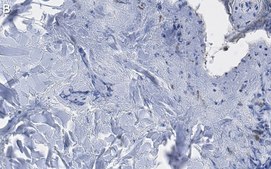

Immunohistochemistry (Paraffin) Analysis: A 1:100 dilution from a representative lot detected Collagen Type III in human skin tissue sections.